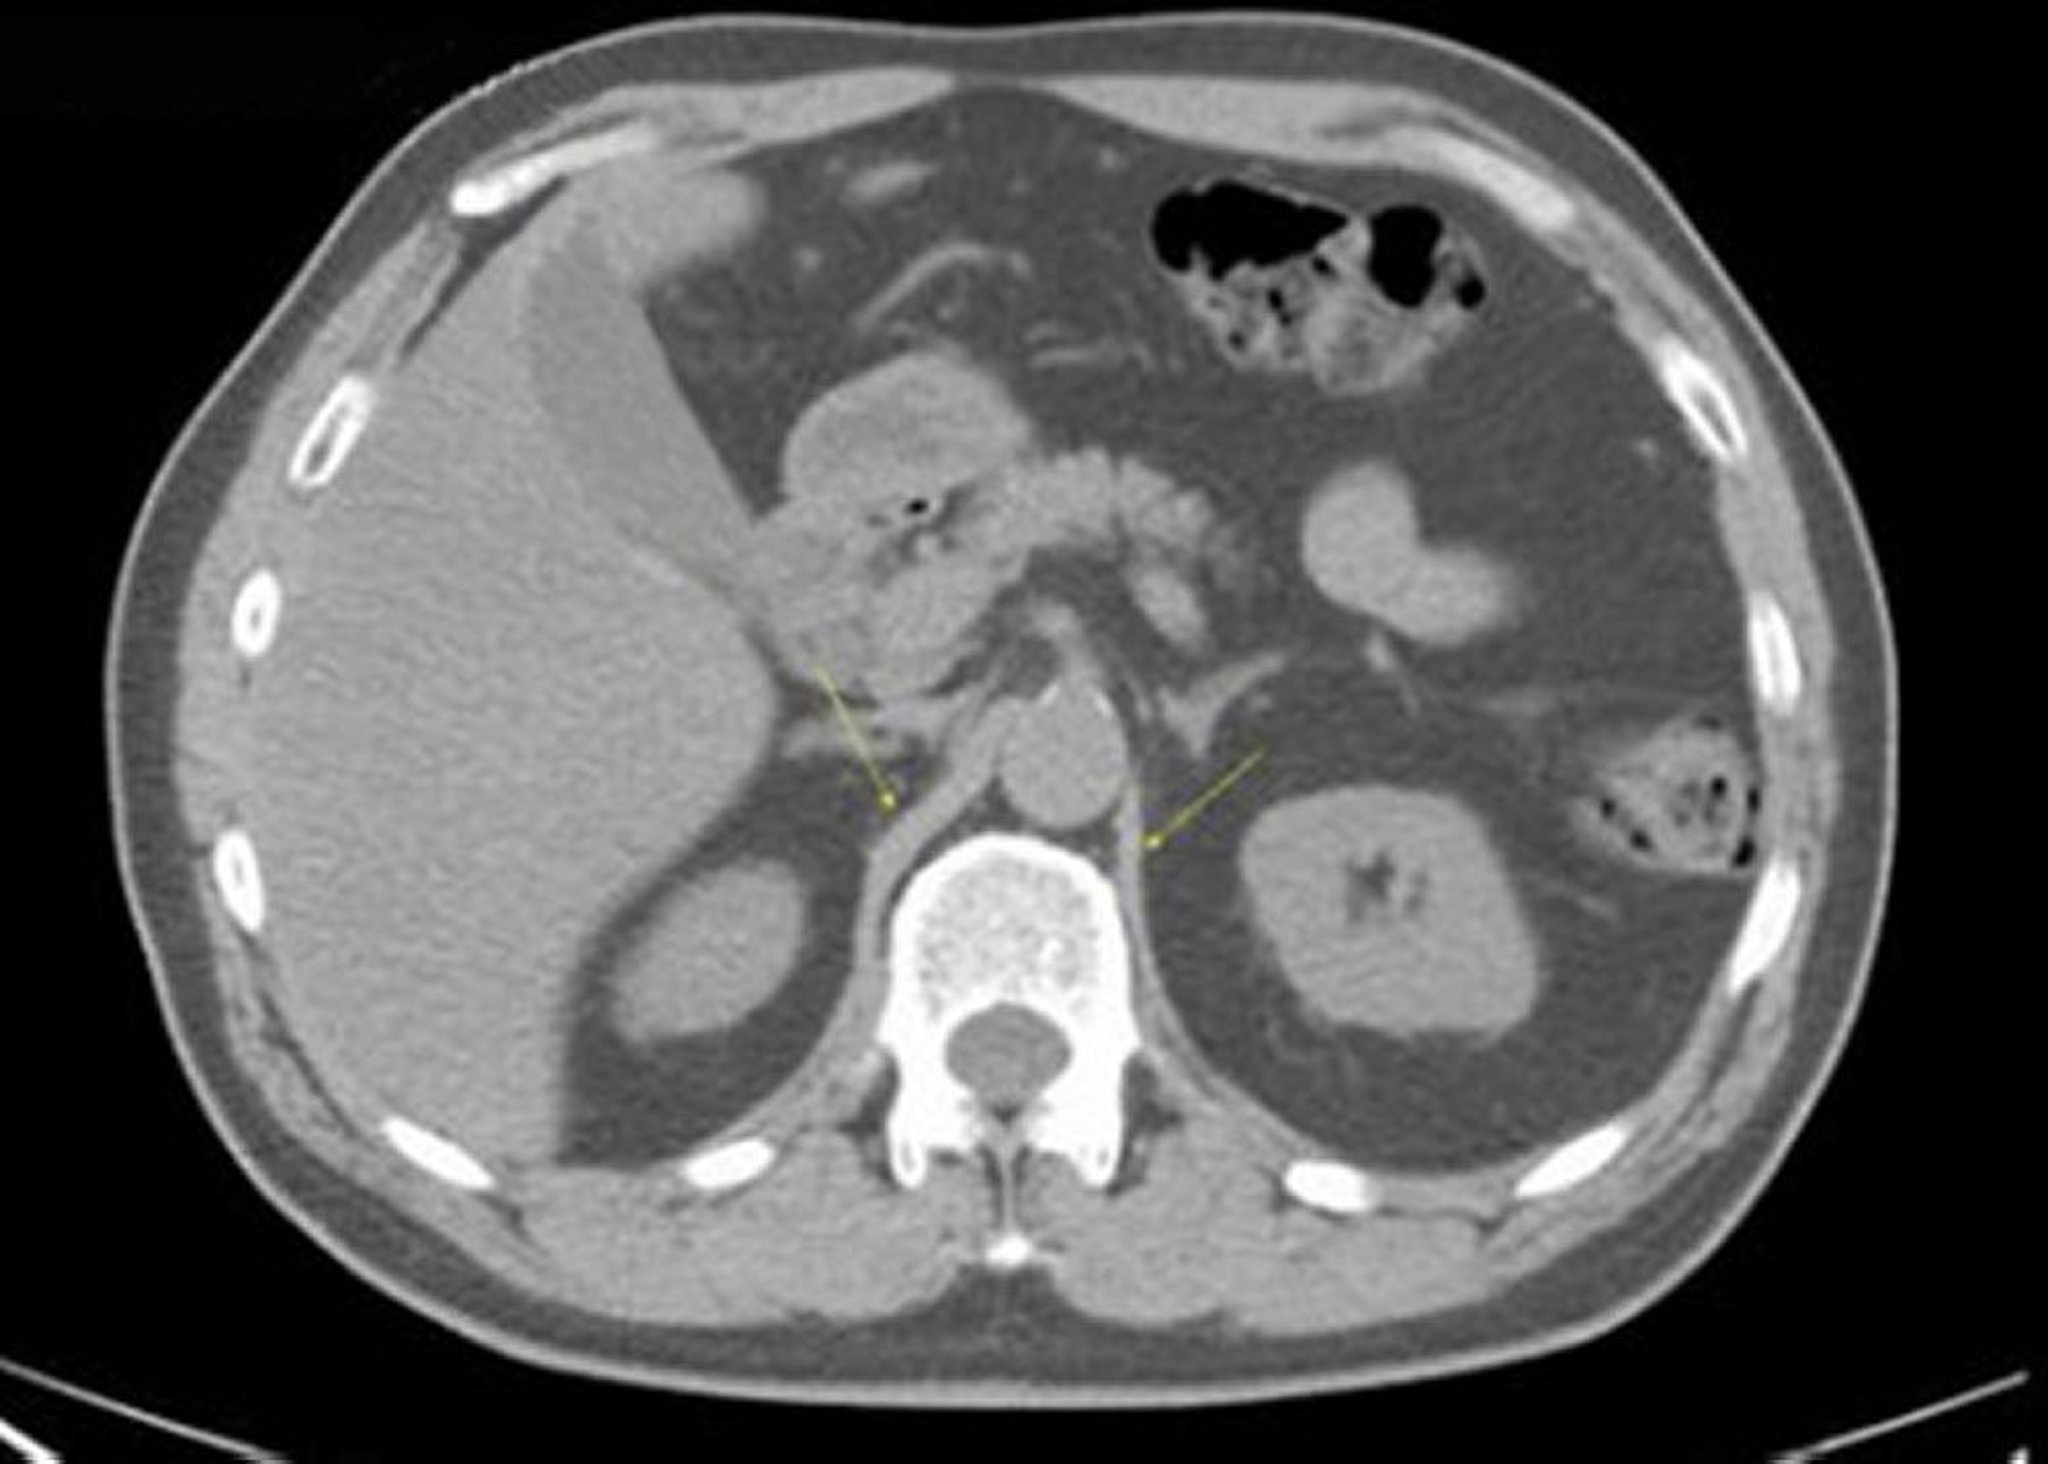

Noncontrast CT Scan of the Abdomen and Pelvis Showing Normal Anatomy (Slide 10)

This image shows the crura of the diaphragm (arrows).